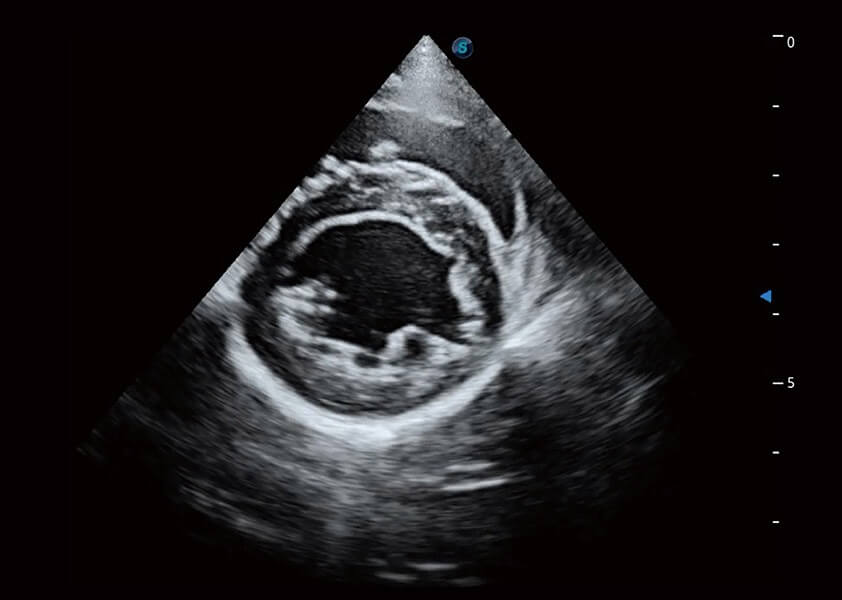

ProPet 60 作为一款高端台式动物超声设备,为动物医生的日常诊断提供了一系列贴合动物临床需求、解决临床实际问题的高级成像功能。凭借全系列高清探头,满足医生对腹部、心脏、生殖、浅表、肌骨等成像的所有需求,切实帮助您提升检查效率,提高诊断信心。

兽用彩色多普勒超声诊断系统

动物是人类最亲密的朋友和最值得信赖的伙伴。新葡的京集团8814检测站也一直致力于探索动物专用的超声影像解决方案。 全新推出的ProPet系列,是新葡的京集团8814检测站在动物超声影像智能化、专业化、精准化的一次跨越式革新。动物不能用言语来表述自己的不适,通过超声影像,ProPet系列搭建了动物医生与不同物种沟通的“桥梁”,为动物医生注入了“治愈之力”。